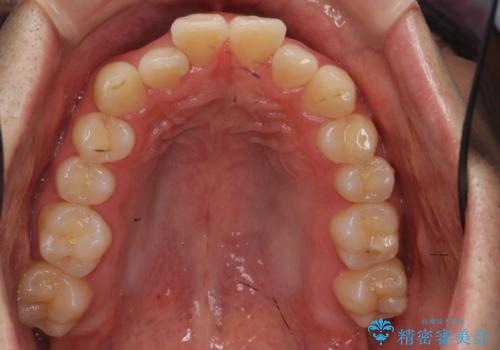

前歯のがたつき マウスピース矯正で 非抜歯で奥歯を後ろに下げる治療

- 前歯のがたつきを主訴に来院。

歯を抜かずに、奥歯を後ろに下げ、歯の両側をわずかに削って並べました。

奥歯を後ろに下げるのに、上下左右に矯正用ミニスクリューを入れています。

歯のがたつきがなくなると、歯ブラシがしやすくなり、茶色いステインも付きにくくなります。